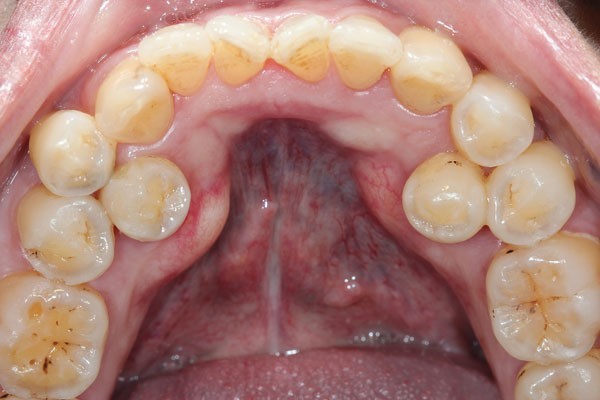

Impacted canines (49%)

Supernumeraries (16%)

Impacted second premolars (10%).

In addition to the service analysis described in part 1 of the BDJ series, in part 2 the authors provide an overview of common dental anomalies. Their definition, classification, aetiology and prevalence have been outlined along with their diagnosis and management. The aim of this is to increase awareness amongst practitioner's and help them formulate appropriate treatment plans. Part 1 of the series covers soft tissue anomalies, dentigerous cysts, transpositions and supernumerary teeth. Whereas part 2 focuses on impacted teeth, delayed and failed eruption, ankylosed incisors and infra-occluded deciduous molars.

The average age of patients presenting to the clinic with impacted canines was 17 years, this is a late presentation age. Impacted canines are a common dental anomaly and although there are a number of reasons for late referral, this service evaluation has highlighted an area where knowledge improvement may be beneficial. The age of presentation for unerupted central incisors was also late. We hope that the information presented in this two part series is useful for the whole dental team.